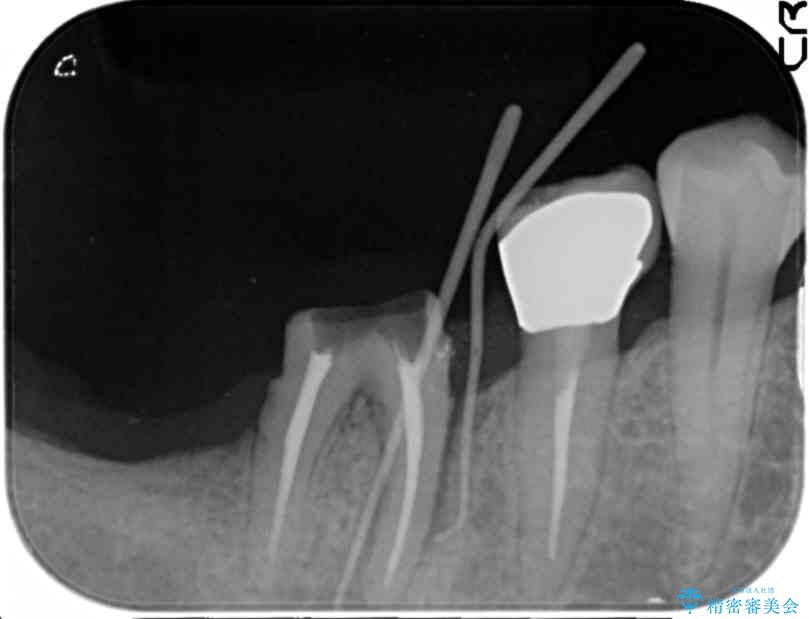

来院主訴

「奥歯で噛むと痛い、いつも膿のにおいがして不快、改善してほしい。」と治療を希望され来院されました。

精査した結果、奥歯の根は破折しており抜歯を避けられない状況でした。

治療前

奥歯から膿のにおいがする インプラントによる機能回復 治療前画像 奥歯から膿のにおいがする インプラントによる機能回復 治療前画像 奥歯から膿のにおいがする インプラントによる機能回復 治療前画像 奥歯から膿のにおいがする インプラントによる機能回復 治療前画像 奥歯から膿のにおいがする インプラントによる機能回復 治療前画像 奥歯から膿のにおいがする インプラントによる機能回復 治療前画像